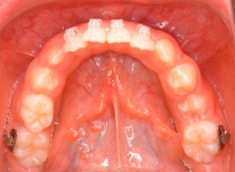

治療後(1年3ヶ月後)